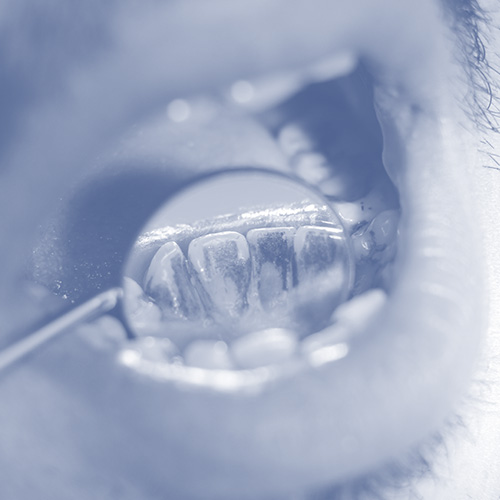

A cavity is a permanently damaged area in a tooth caused by poor dental hygiene, bacteria, and keeping a diet of sugary foods or drinks. Left untreated, tooth decay and worsening dental health lead to damage to your teeth and enamel. Composite fillings are a routine dental procedure, usually completed in one appointment. After numbing the gums surrounding the tooth before repair, Dr. Dimitri Salin will remove the decayed part of the tooth to restore it fully. It is possible to save a lot more of the tooth with composite and porcelain fillings than older amalgam fillings allowed. Once a space is created for the new filling, it will be cleaned and shaped before adding its filling. Then the composite will be inserted, compacted, and polished. The composite is cured by shining a specialized light on the new filling, restoring dental health.